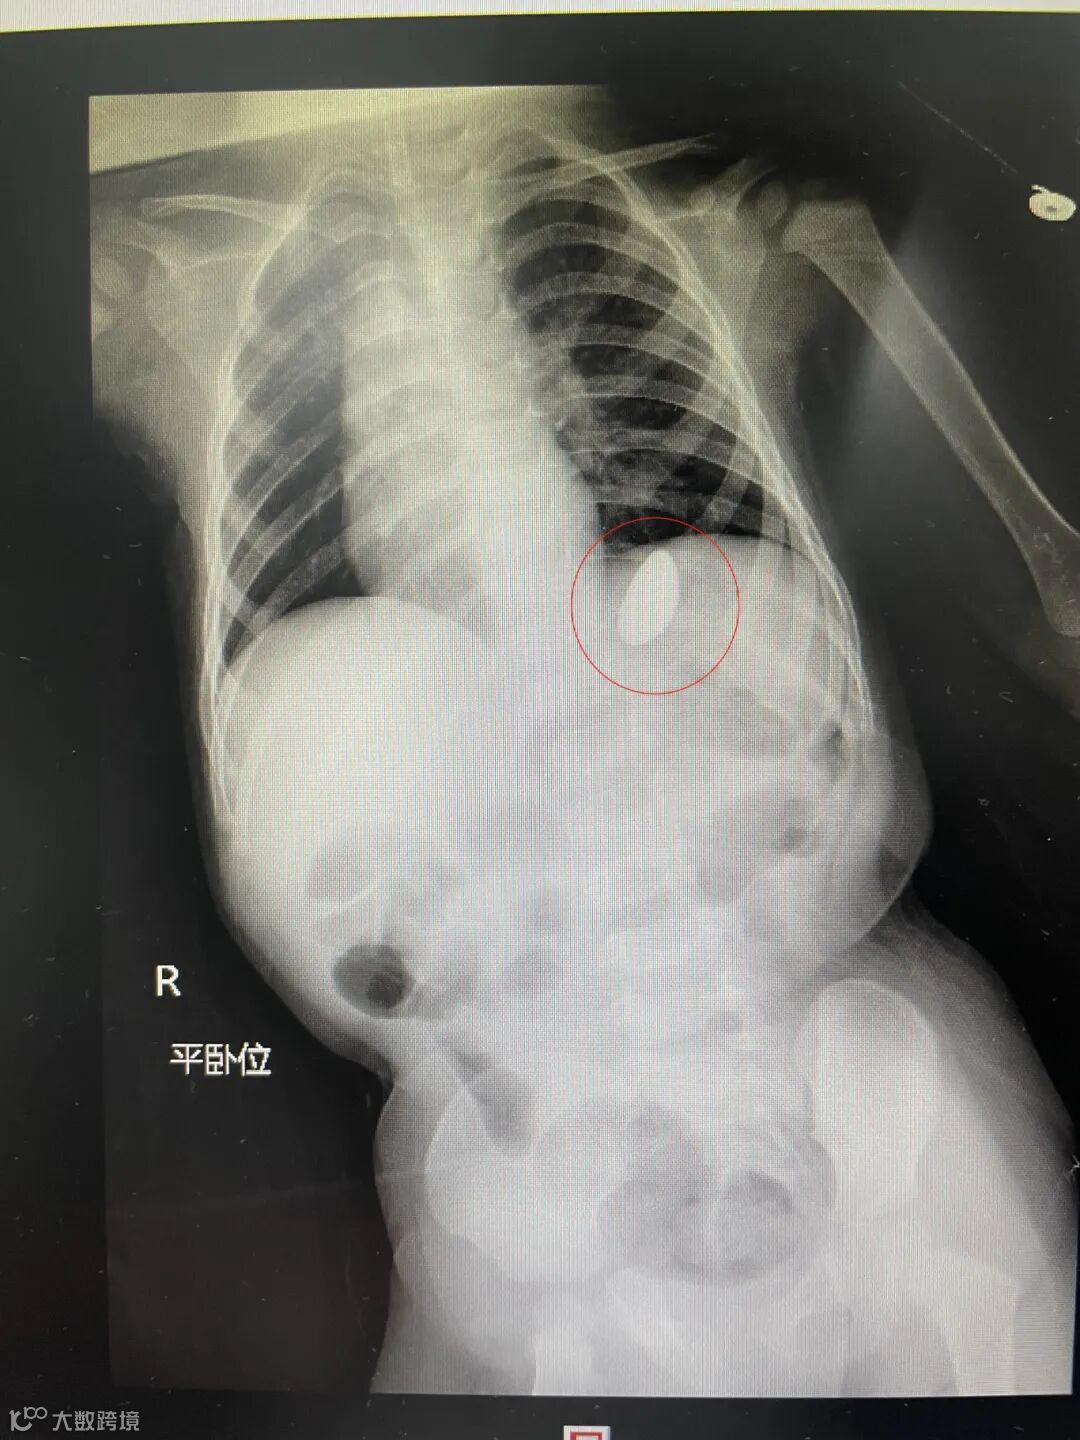

做好术前准备后,耳鼻喉头颈外科洪元庚主任医师和欧俊良住院医师开始为小朋友进行手术,可是当食道镜进入食道后却没有发现异物,再次经过术中拍片检查,显示异物已经到了小朋友的胃里面了。

于是两人立即联系消化内科医生进行会诊,消化内科副主任医师梁少旭来到手术室后,通过胃镜进入,在胃腔中发现了石头的踪影,大小约为2.5cmX3.7cm,梁少旭利用一次性取石网,小心翼翼地将石头取出,再次进镜观察,所见胃腔无活动性出血,未见明显穿孔,术后小朋友无任何不适症状,目前正在耳鼻喉科进行消炎治疗。